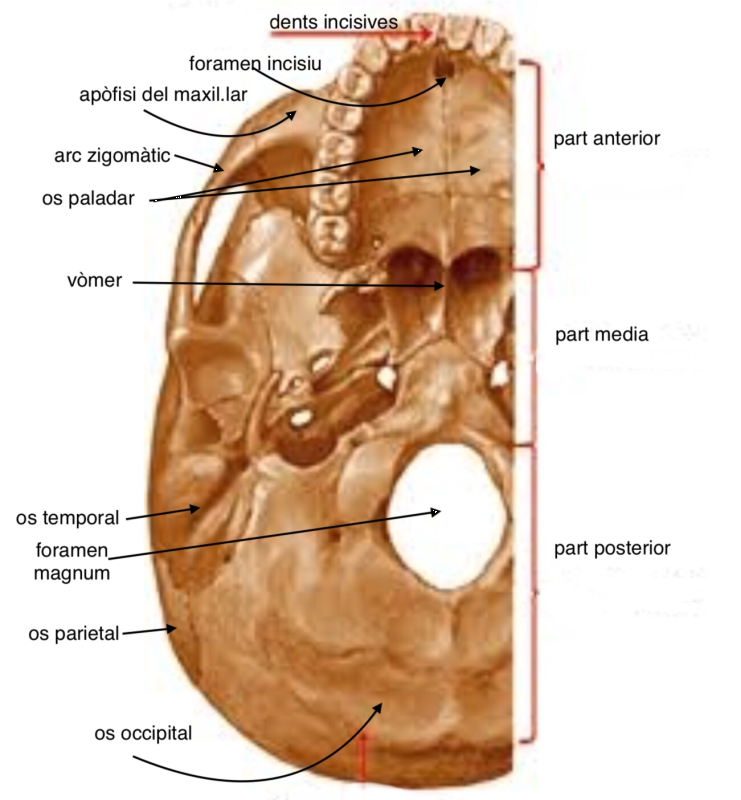

L’esquelet axial està format pels ossos localitzats al voltant de l’eix vertical (en posició anatòmica) i es troba als ossos del cap, coll i tronc; vegeu la figura:

- Crani: ocupa una posició superior a la columna vertebral i és l’estructura que protegeix l’encèfal. Juntament amb els ossos de la cara, forma el cap. S’articula amb la columna vertebral a través d’un gran orifici, el foramen magnum, que es troba en una posició basal. Vegeu els ossos principals del crani en una visió lateral (esquerra), a la figura, i en una visió basal (part exterior), a la figura: